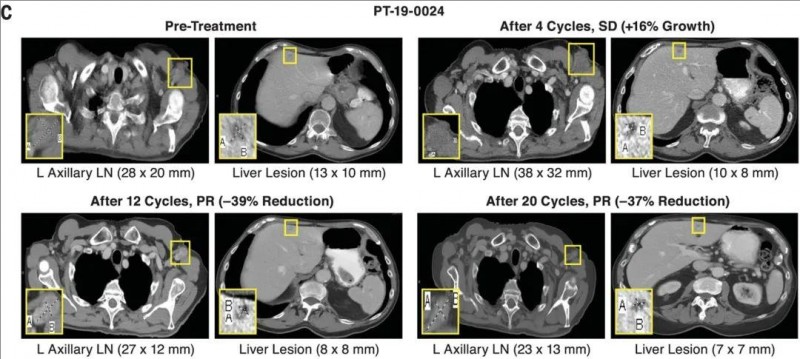

研究特别展示了2例应答患者的影像资料,用可视化证据直击震撼疗效。

其中患者PT-19-0024,CT影像清晰记录其“逆袭之路”:尽管FMT治疗初期肿瘤短暂增长,但随后逐渐退缩,最终实现部分缓解(PR)。

▼PT-19–0024患者代表性CT图像